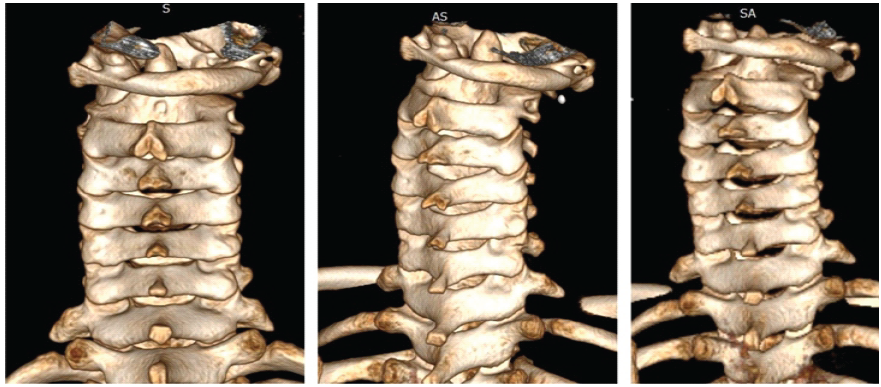

Plain radiographs demonstrated asymmetry of the lateral masses. Computed tomography (CT) scan confirmed Fielding Type II C1–C2 rotatory subluxation with anterior displacement of C1 (Fig. 2 and 3). Magnetic resonance imaging (MRI) showed persistent malalignment without spinal cord compression (Fig. 4).

Figure 3: Pre-operative computed tomography scan with three-dimensional reconstruction showing persistent rotation of the atlas (C1) relative to the axis (C2), consistent with Fielding Type II atlantoaxial rotatory subluxation.